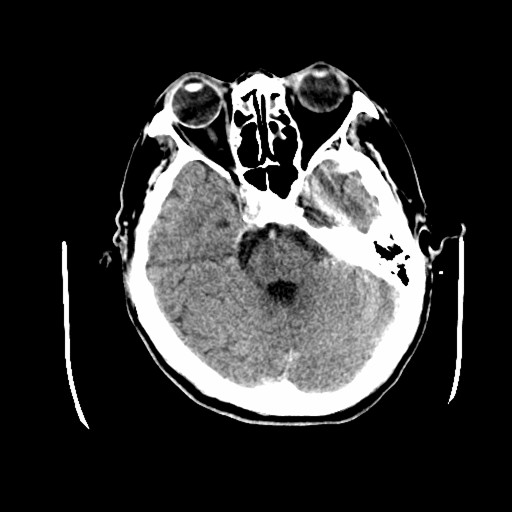

标题: CT19998:男,68岁,突然偏瘫一天 [打印本页]

标题: CT19998:男,68岁,突然偏瘫一天

右侧额叶梗塞

1天梗塞密度也太低点了吧,不除外占位性病变,建议增强.

考虑占位,1级胶质瘤?

分水岭区梗塞

多考虑占位,右侧脑室前角受压。

考虑右侧额顶叶脑梗塞。

支持梗塞表现

好像只能以梗死来解释。